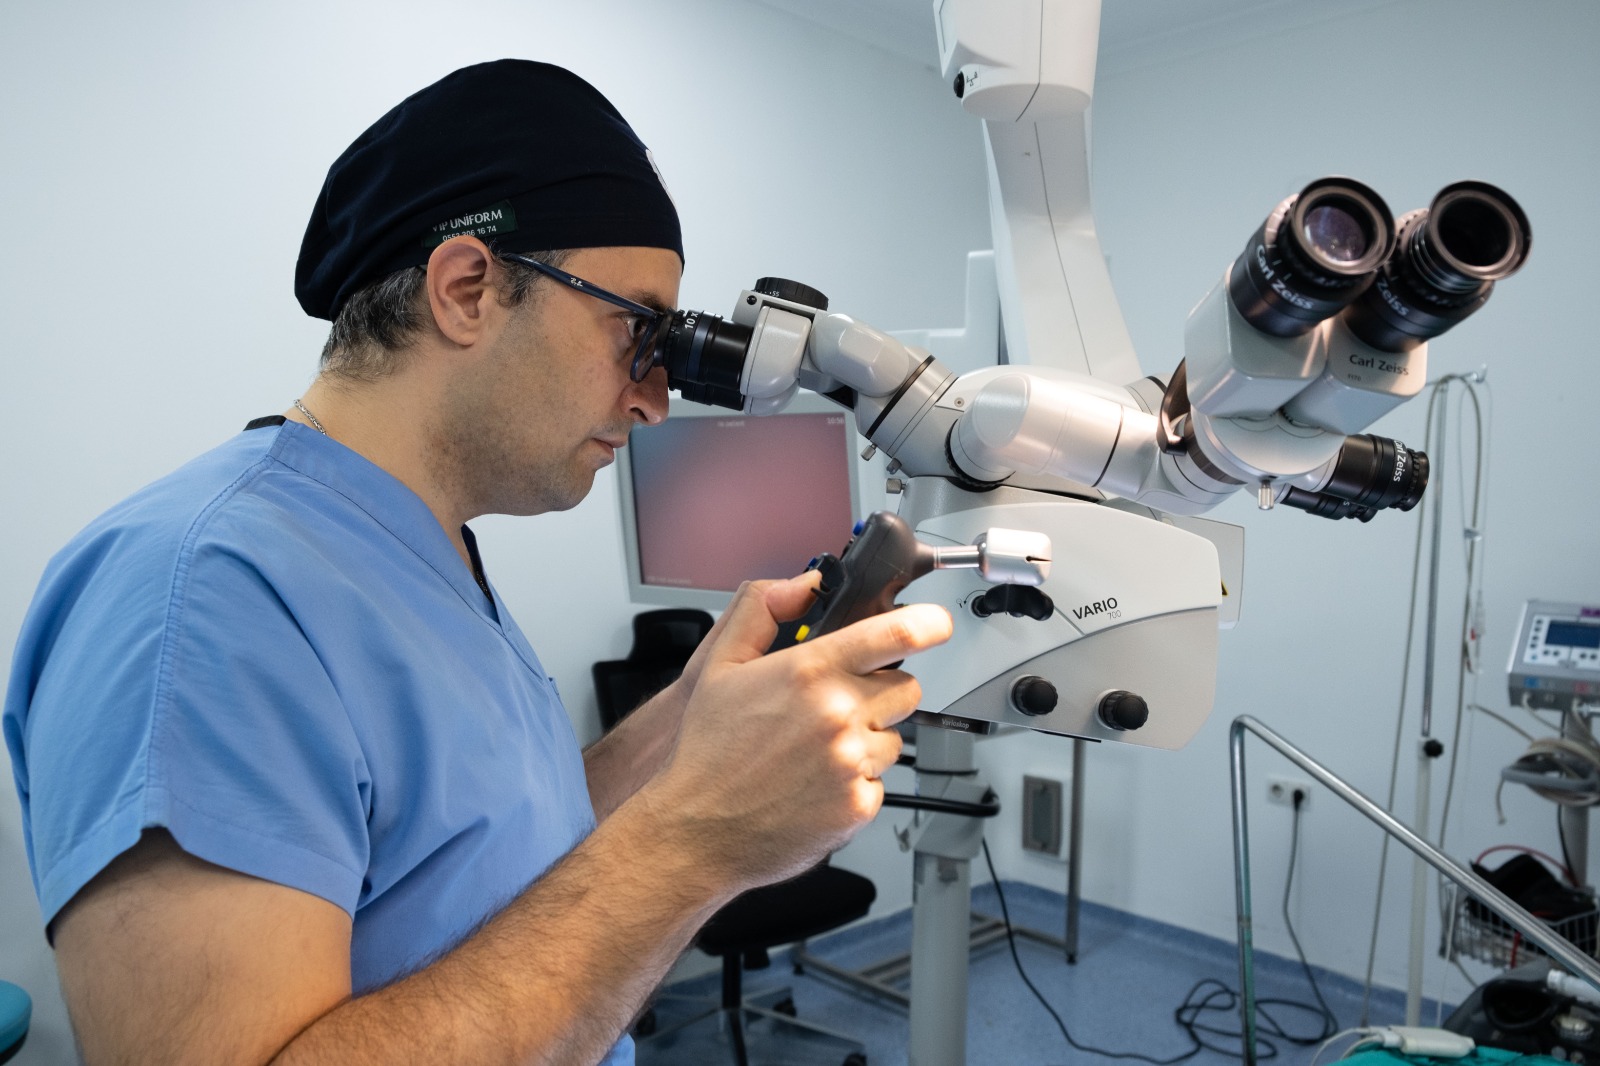

OP. DR. EMRE YURDAKUL: ORTOPEDİDE AMERİKA’YLA EŞ DEĞER DURUMDAYIZ

Sağlık turizminde son yıllarda ülke olarak ulaştığımız seviye, büyük dikkat çekerken Kayseri System Hospital doktorlarından Op. D […]